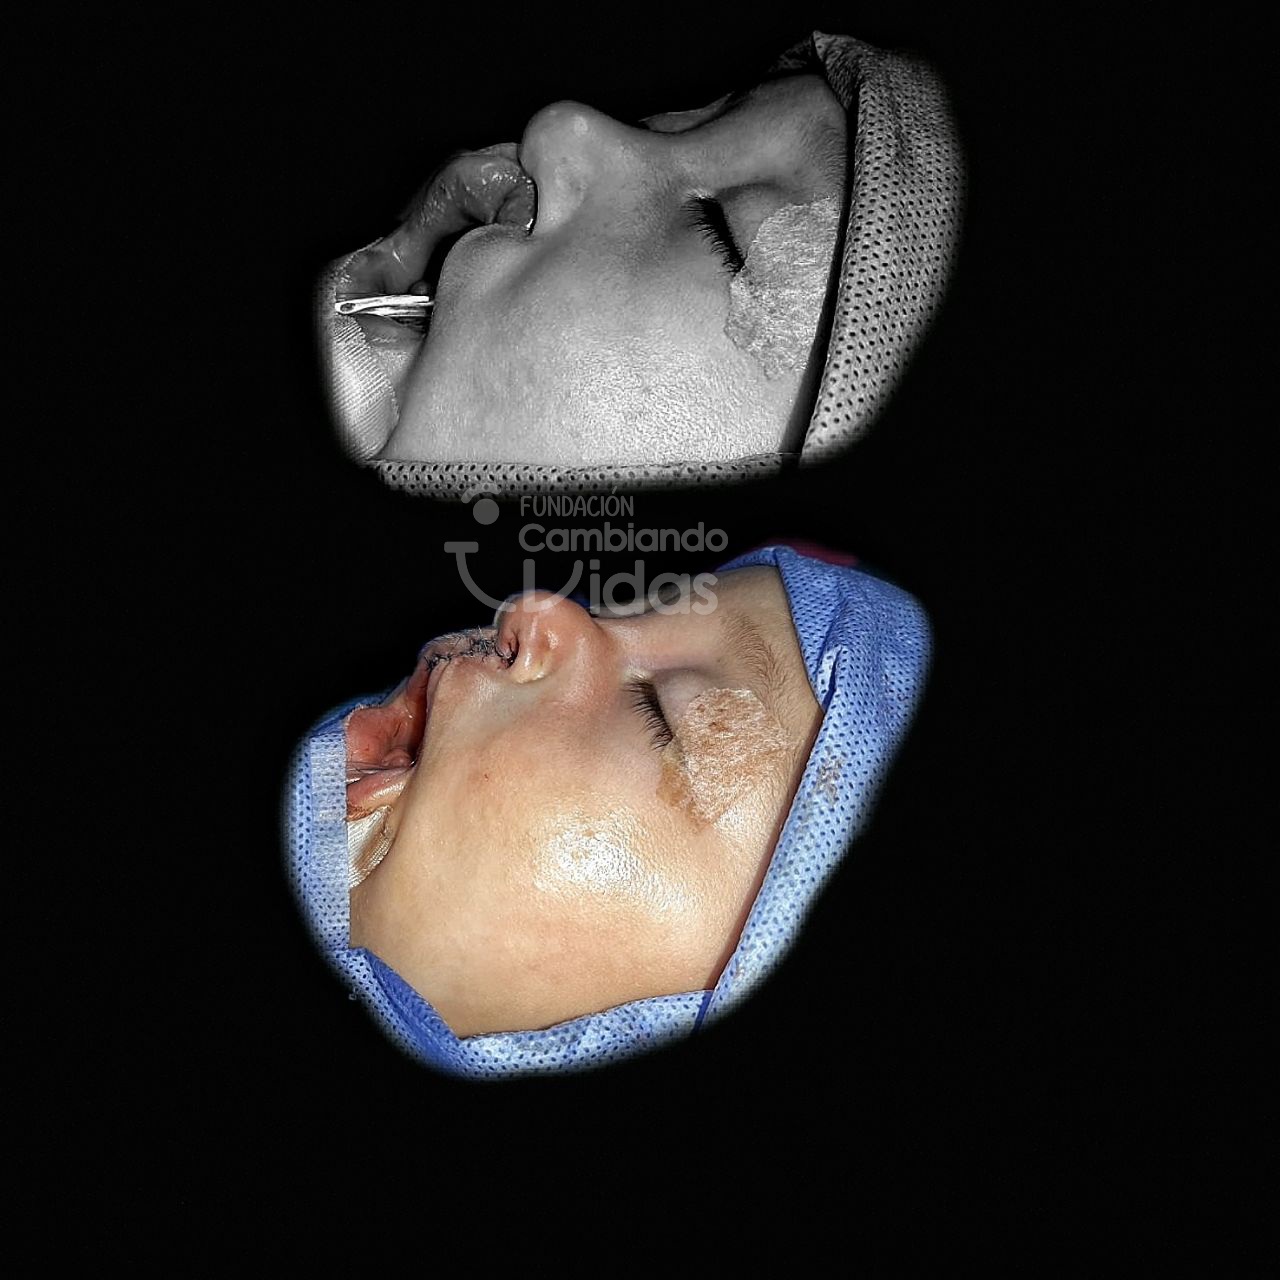

Paula Díaz

Intervención Quirurgica: Rinoqueiloplastia Secundaria y Palatoplastia Primaria